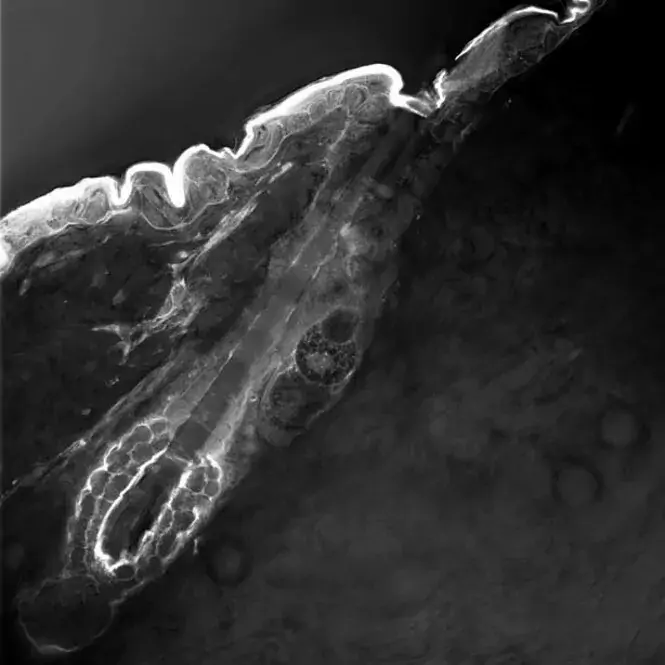

En bild säger mer än tusen (komplicerade) ord. Utställningen Den osynliga kroppen använder visualisering som kunskapsbärare och utgångspunkt för att berätta om medicinsk forskning i framkant.

KI-forskarnas bidrag till Den osynliga kroppen donerades till KI efter utställningens slut av Ragnar Söderbergs stiftelse och de hänger idag i Biomedicums lokaler. Här kan du läsa mer om de enskilda verken.